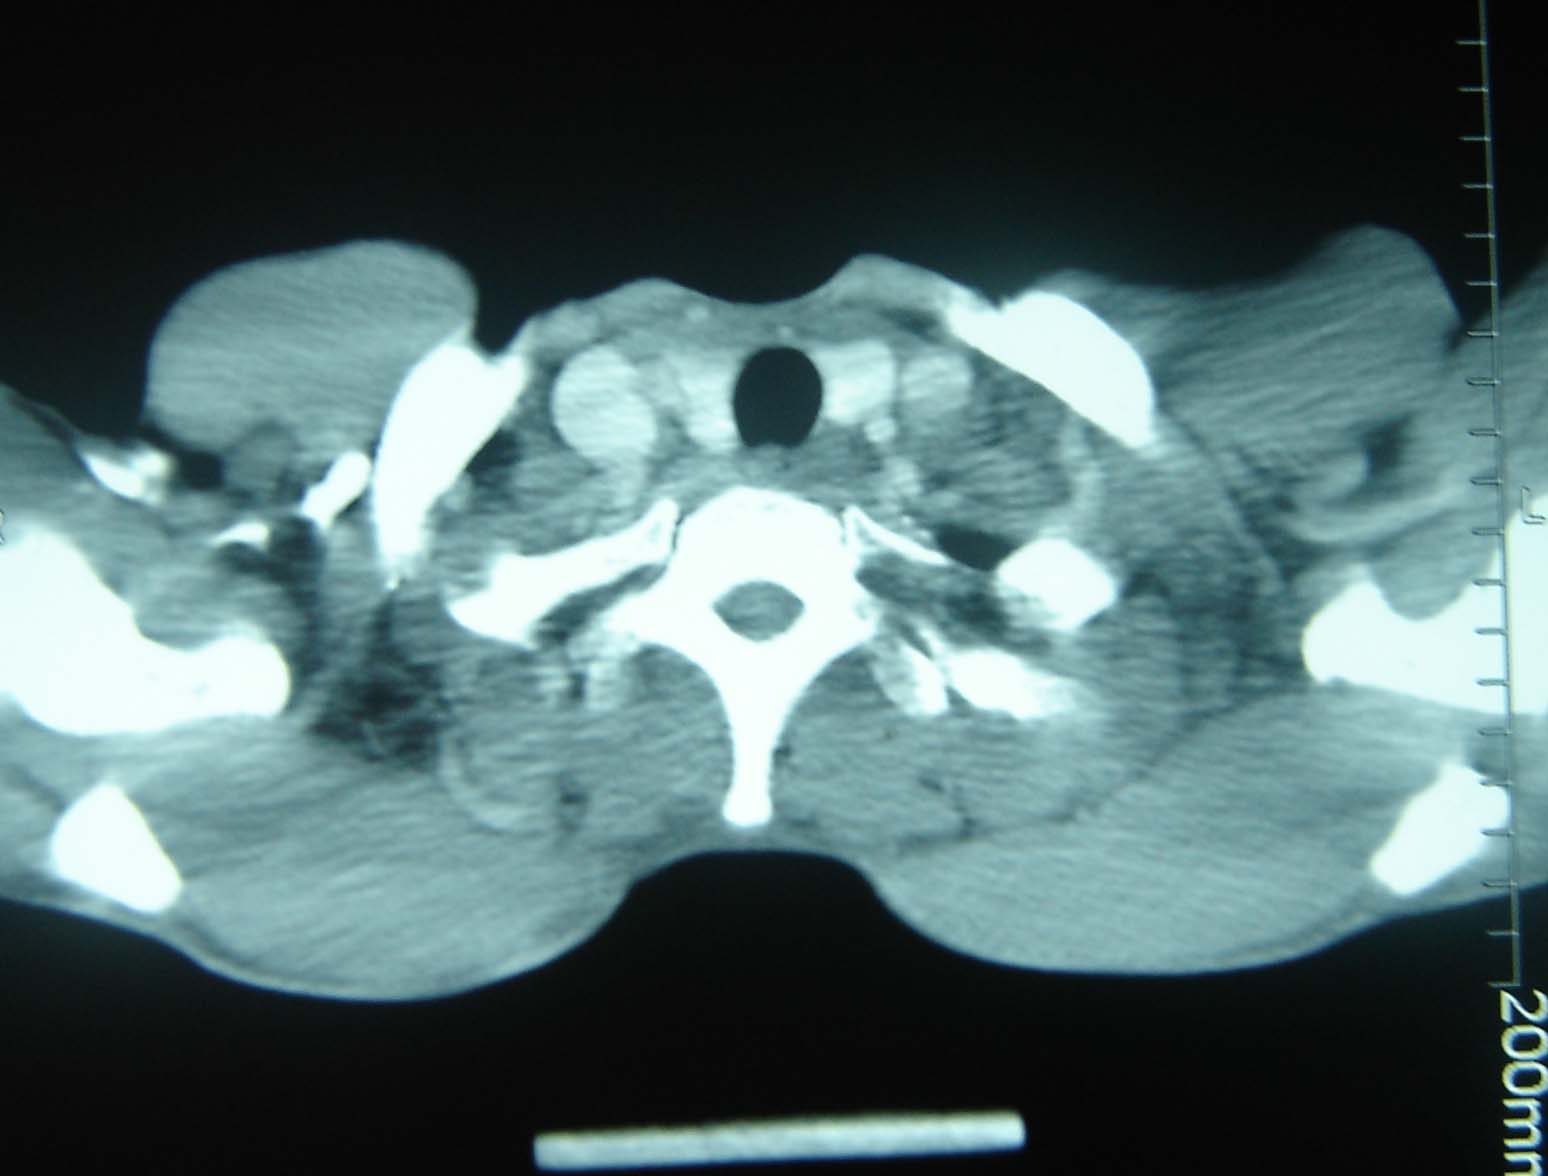

标题: CT25321:两肺多发结节 请会诊 [打印本页]

标题: CT25321:两肺多发结节 请会诊

男 、43岁,咳嗽胸痛,装修工,平时接触粉尘较多,有吸烟史10多年,纤维支气管镜检查未发现异常,胃镜、腹部b超检查亦未发现异常,颈部淋巴结活检未发现肿瘤细胞。

结节病?转移瘤?

1)考虑双肺及胸膜多发性转移瘤。2)肺气肿。